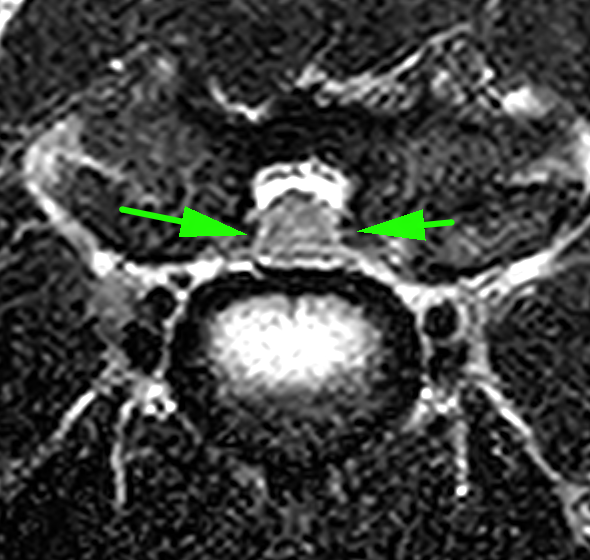

MRI画像検査です。頚椎2−3の圧迫が確認されました。

頚椎3−4での圧迫が確認されました。